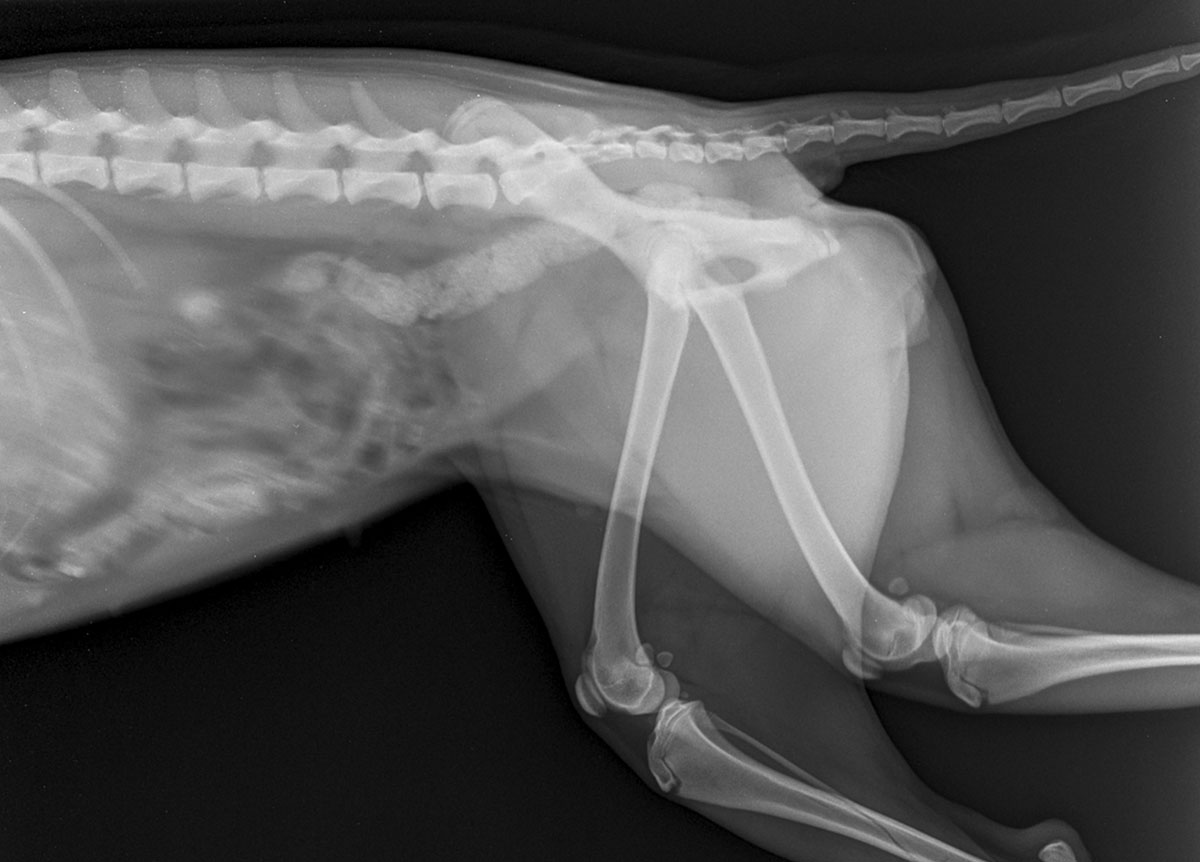

Dr. Bernd Tellhelm: Kritik am Verbot für Hunde mit „Qualzuchtmerk-malen“ bei Sport-veranstaltungen

In seiner Stellungnahme zum Verbot für Hunde mit „Qualzuchtmerkmalen“ an sportlichen Veranstaltungen stellt Dr. Bernd Tellhelm klar, dass erbliche Skelettveränderungen wie HD nicht automatisch zu Schmerzen oder Leiden führen müssen.